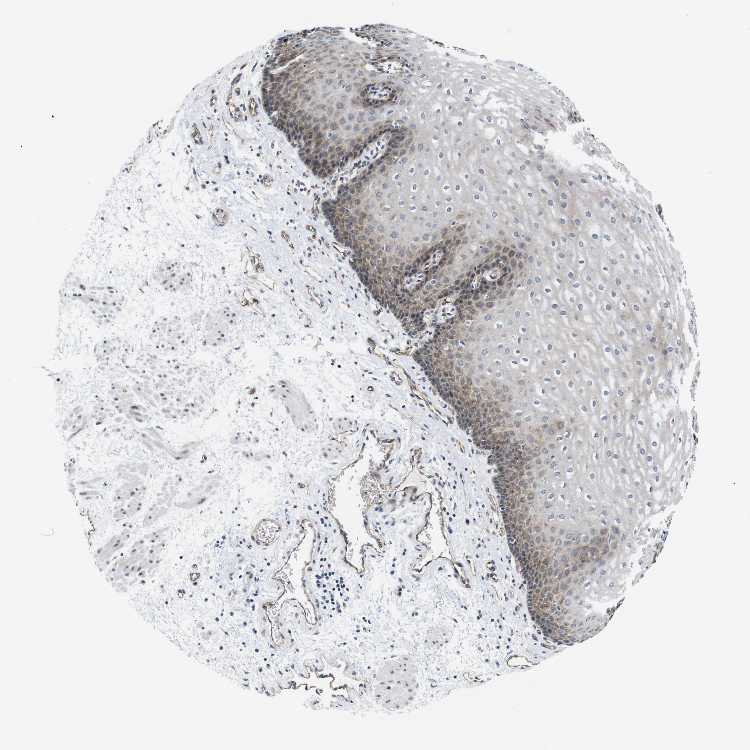

ESOPHAGUS - Antibody stainingi

Antibody staining in the annotated cell types in the current human tissue is reported as not detected, low, medium, or high, based on conventional immunohistochemistry profiling in selected tissues. This score is based on the combination of the staining intensity and fraction of stained cells.

Each image is clickable and will lead to virtual microscopy that enables deeper exploration of all samples and also displays staining intensity scores, fraction scores and subcellular localization as well as patient and tissue information for each sample.

Antibody CAB012220

Squamous epithelial cells Medium